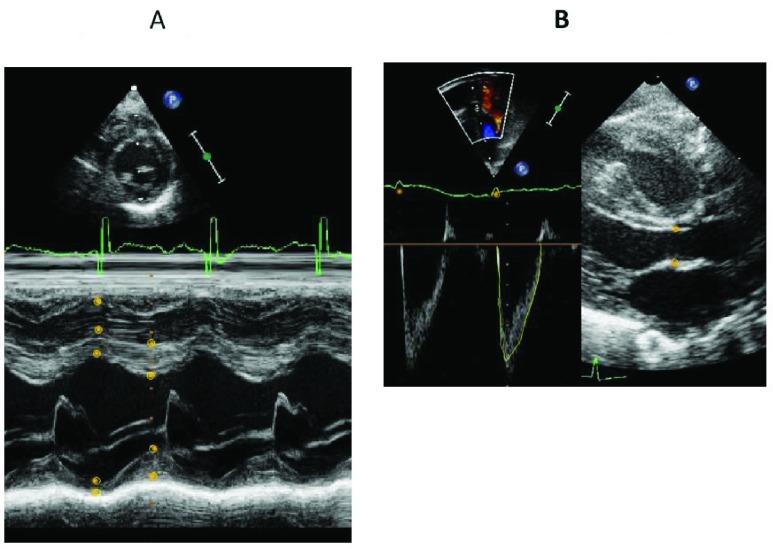

There is a great need for training in pediatric echocardiography. In addition to physicians being trained in pediatric cardiology and echocardiography technologists, neonatologist, pediatric intensivists, and other health care professionals may be interested in such training. Since, there is limited opportunity of training on live patients, echocardiographic simulators may be of help. No simulator with complete range of echocardiographic modalities is available for neonates and infants. The aim of this project was to develop a mannequin-based echocardiographic simulator capable of simulating full range of pediatric 2D, color flow Doppler, spectral Doppler, and M-mode echocardiograms. A mannequin, a laptop computer, a magnetic tracking device, and a six-degree freedom (6DOF) sensor incorporated in a dummy transducer serve as the hardware platform of the simulator. We obtained six to seven 4D echocardiographic datasets in DICOM format through five acoustic windows from each infant along with a complete set of 2D video clips of color flow, Doppler, and M-mode. The 4D datasets are sliced into 3D slices using the visualization toolkit and are displayed as 2D echocardiograms through the information obtained by the 6DOF sensor. The coordinates from specific 3D slices triggers display of video clips of color flow, M-mode, and Doppler echocardiogram. Software written in C++ programming language controls the basic function of the program. The main simulator screen displays the full range of 2D echocardiograms including color flow Doppler, spectral Doppler, and M-mode from each acoustic window, whereas the side screen display the position and motion of the cutting planes through a 3D heart model. The system includes a software module to perform hemodynamic measurements from specific video clips images. Our hybrid, mannequin-based pediatric echocardiography simulator provides full range of pediatric echocardiography training experience. This simulator may help training in pediatric echocardiography for which there is a growing demand in clinical medicine.

小儿超声心动图培训的需求非常大。除了对儿科心脏病学医生和超声心动图技术人员进行培训外,新生儿科医生、儿科重症监护医生和其他医疗保健专业人员也可能对这类培训感兴趣。由于对真实患者进行培训的机会有限,超声心动图模拟器可能会有所帮助。目前还没有适用于新生儿和婴儿的具备完整超声心动图检查方式的模拟器。本项目的目的是开发一种基于人体模型的超声心动图模拟器,能够模拟儿科全范围的二维、彩色血流多普勒、频谱多普勒和M型超声心动图。一个人体模型、一台笔记本电脑、一个磁跟踪设备以及一个集成在虚拟换能器中的六自由度(6DOF)传感器构成了模拟器的硬件平台。我们通过五个声学窗口从每个婴儿身上获取了六到七个DICOM格式的四维超声心动图数据集,以及一套完整的彩色血流、多普勒和M型二维视频片段。使用可视化工具包将四维数据集切片成三维切片,并通过六自由度传感器获取的信息将其显示为二维超声心动图。来自特定三维切片的坐标触发彩色血流、M型和多普勒超声心动图视频片段的显示。用C++编程语言编写的软件控制程序的基本功能。模拟器主屏幕显示来自每个声学窗口的包括彩色血流多普勒、频谱多普勒和M型的全范围二维超声心动图,而侧屏幕通过三维心脏模型显示切割平面的位置和运动。该系统包括一个软件模块,用于从特定视频片段图像中进行血流动力学测量。我们基于人体模型的混合型小儿超声心动图模拟器提供了全范围的小儿超声心动图培训体验。该模拟器可能有助于小儿超声心动图的培训,而这在临床医学中的需求日益增长。